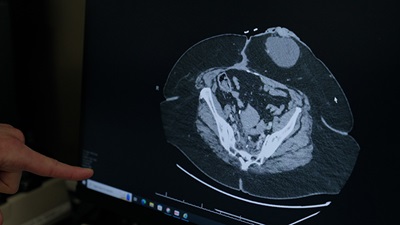

Laparoscopic and robotic surgery for colon and rectal cancer

Our surgeons excel in minimally invasive surgeries for colorectal cancer. In fact, Henry Ford was among the first programs in Michigan to offer robotic-assisted colorectal surgery.

We remove tumors without damaging nearby structures, greatly reducing the risk of bowel, urinary or sexual dysfunction. Minimally invasive surgery also helps you recover faster and with less pain.

- Robotic-assisted surgery: Your surgeon controls a robotic arm that removes tumors with incredible precision.